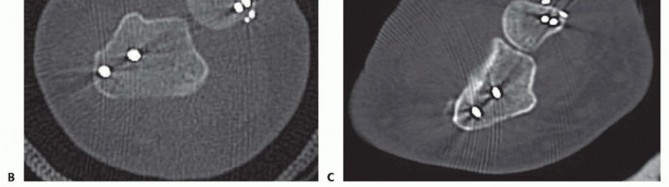

FIG 3 • A. Radioulnar ratio method to measure DRUJ subluxation on a CT scan. See text for details. B. Axial CT scan demonstrating dorsally dislocated ulna following ulnar styloid open reduction internal fixation (ORIF). C. Axial CT scan following reduction and pinning of the dislocated DRUJ. (A: Adapted from Lo IK, MacDermid JC, Bennett JD, et al. The radioulnar ratio: a new method of quantifying DRUJ subluxation. J Hand Surg Am 2001;26:236-243.)